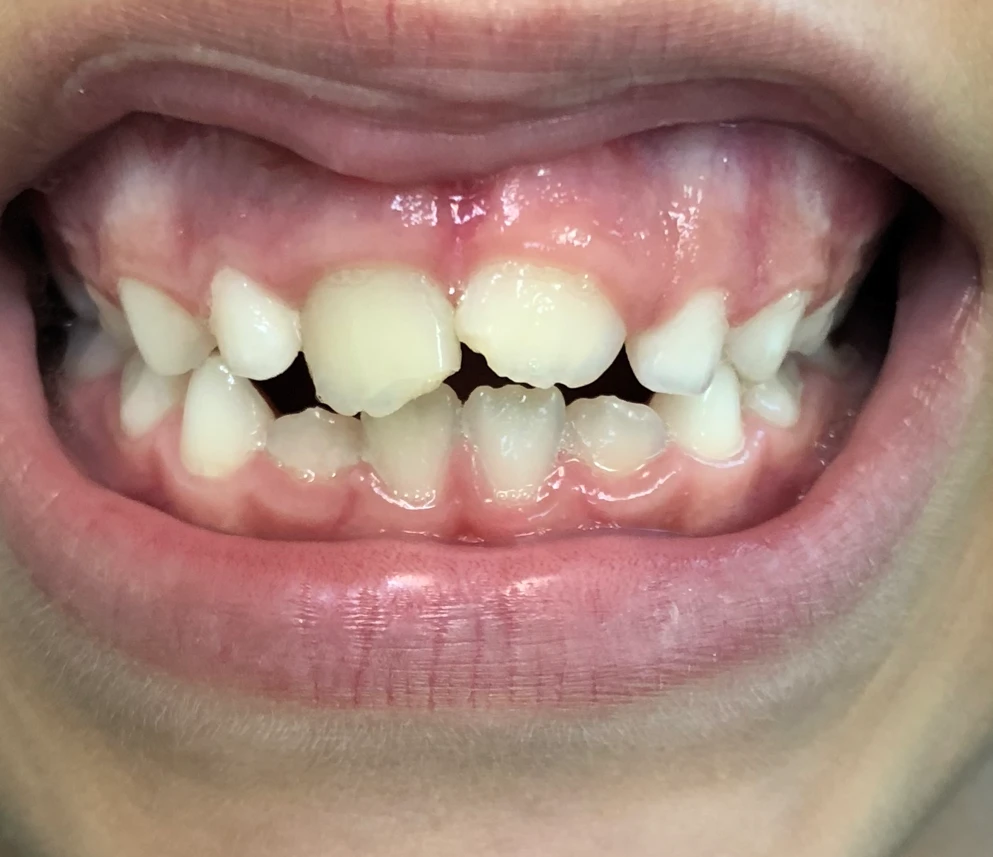

Paciente com 8 anos de idade, compareceu ao consultório com fístula em região vestibular e leve escurecimento em dente 11 (figura 1). Foi realizado o exame clinico e radiográfico (radiografia periapical) na qual foi observado o ápice aberto desse dente (figura 2). No teste de sensibilidade com gás refrigerante o dente apresentou vitalidade negativa.